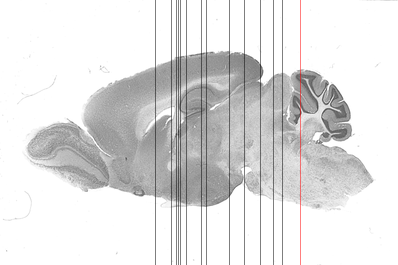

cerebellar cortex lobe (Cb lobe)

Coronal sections Sagittal sections 3D Cross section